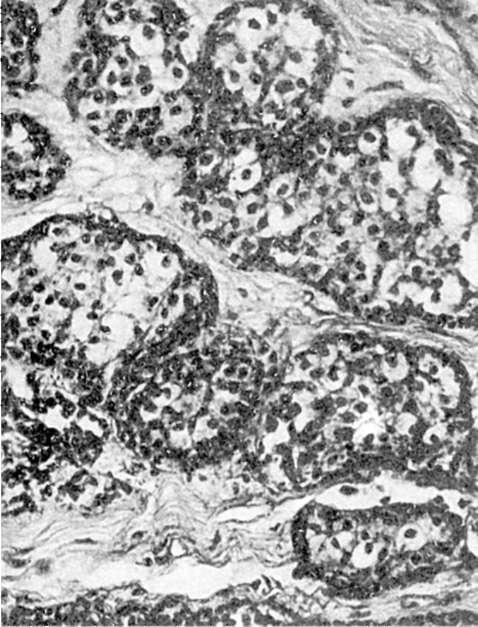

Неинфильтрирующий дольковый рак (дольковый «рак на месте») возникает мультицентрично, имеетсолидный и железистый варианты (рис. 109). Развивается в неизмененной дольке или на фоне дисгормональной доброкачественной дисплазии. Возможен переход в инвазивную форму рака.

Рис. 109. Дольковый

рак молочной железы